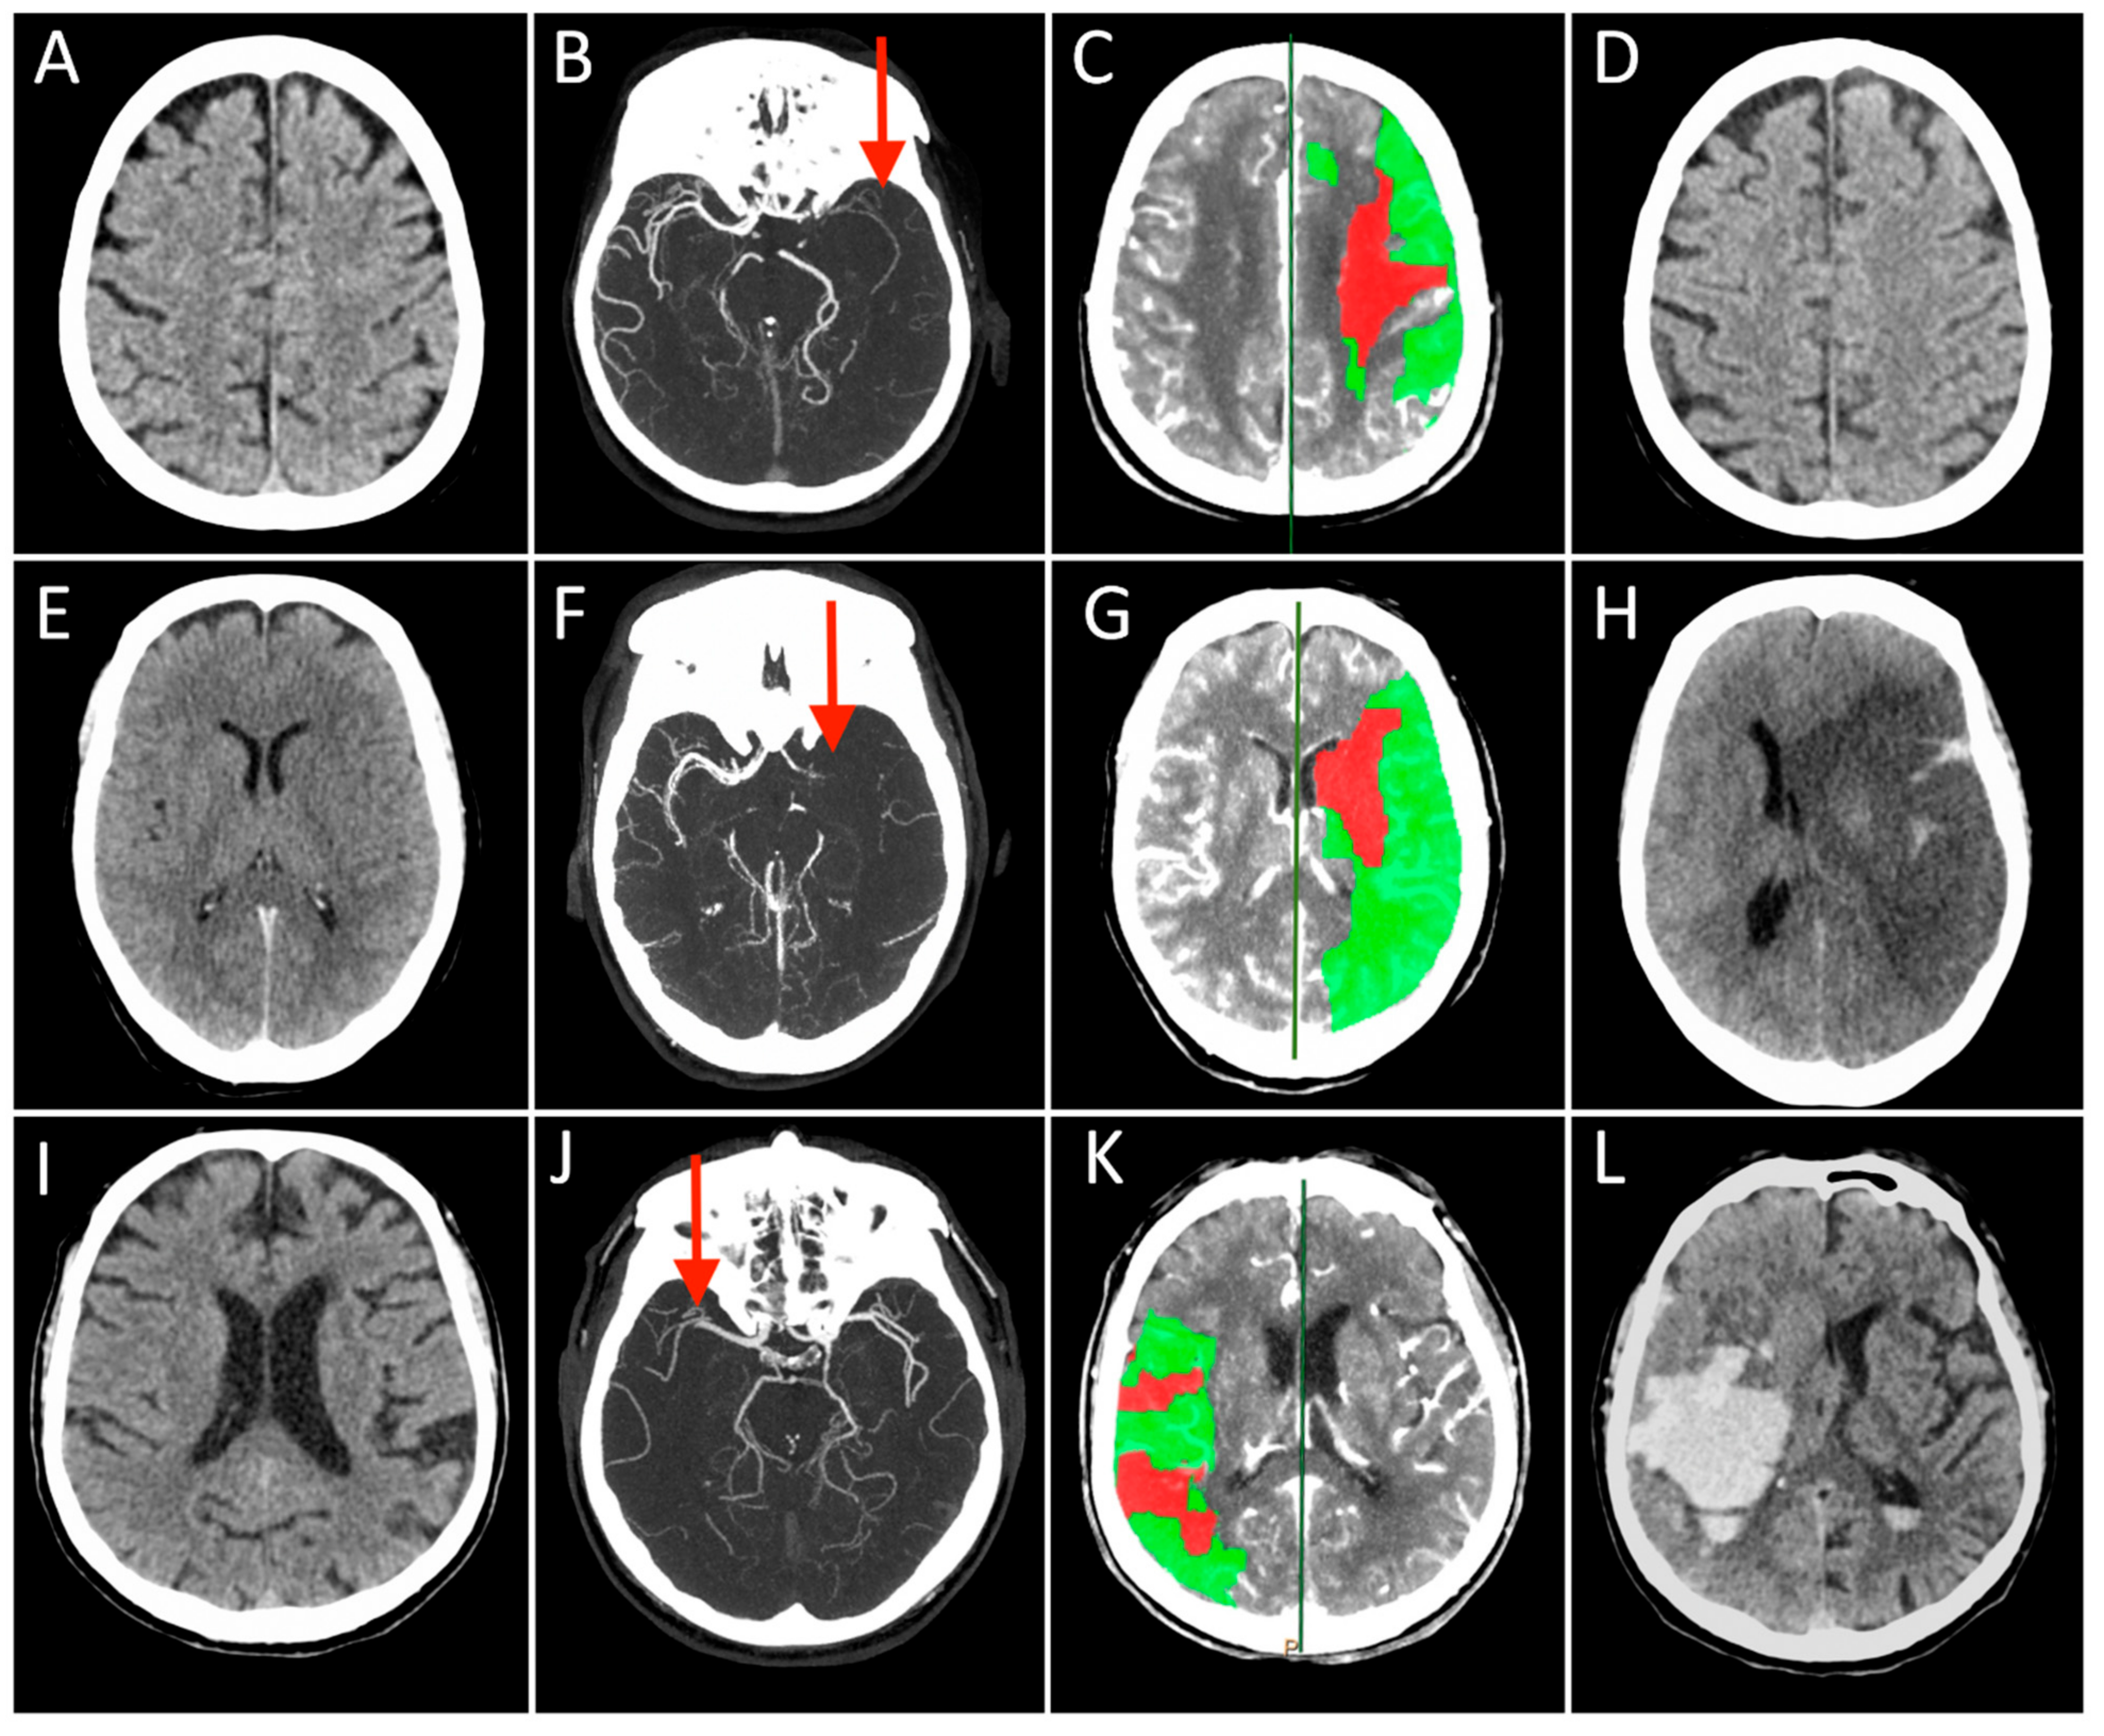

- Leiva-Salinas, C.; Jiang, B.; Wintermark, M. Computed Tomography, Computed Tomography Angiography, and Perfusion Computed Tomography Evaluation of Acute Ischemic Stroke. Neuroimaging Clin. N. Am. 2018, 28, 565–572. [Google Scholar] [CrossRef]

- Menon, B.K.; d’Esterre, C.D.; Qazi, E.M.; Almekhlafi, M.; Hahn, L.; Demchuk, A.M.; Goyal, M. Multiphase CT Angiography: A New Tool for the Imaging Triage of Patients with Acute Ischemic Stroke. Radiology 2015, 275, 510–520. [Google Scholar] [CrossRef]

- Wintermark, M.; Flanders, A.E.; Velthuis, B.; Meuli, R.; van Leeuwen, M.; Goldsher, D.; Pineda, C.; Serena, J.; van der Schaaf, I.; Waaijer, A.; et al. Perfusion-CT assessment of infarct core and penumbra: Receiver operating characteristic curve analysis in 130 patients suspected of acute hemispheric stroke. Stroke 2006, 37, 979–985. [Google Scholar] [CrossRef]